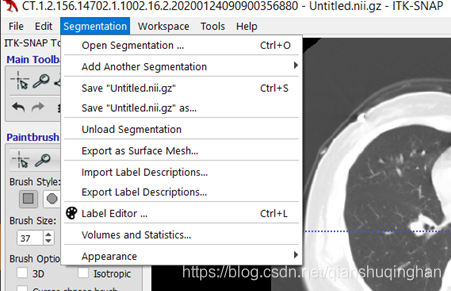

从菜单栏Segmentation->Save Segmentation Image ... (此前无标注结果) or

此前有标注结果:Save “Untitled.nii.gz”(直接覆盖)or 另存为Save “Untitled.nii.gz” as ... 保存为其他文件